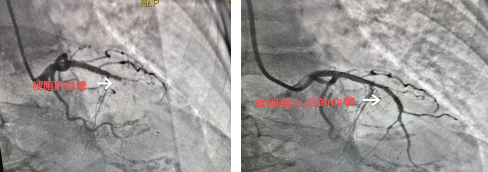

2022年11月25日,李方安主任、蔡波副主任和兰卡初护师仅用时38分钟为患者成功完成了冠状动脉造影术及冠状动脉支架植入术,在科室继续治疗5天后,11月30日患者痊愈出院。